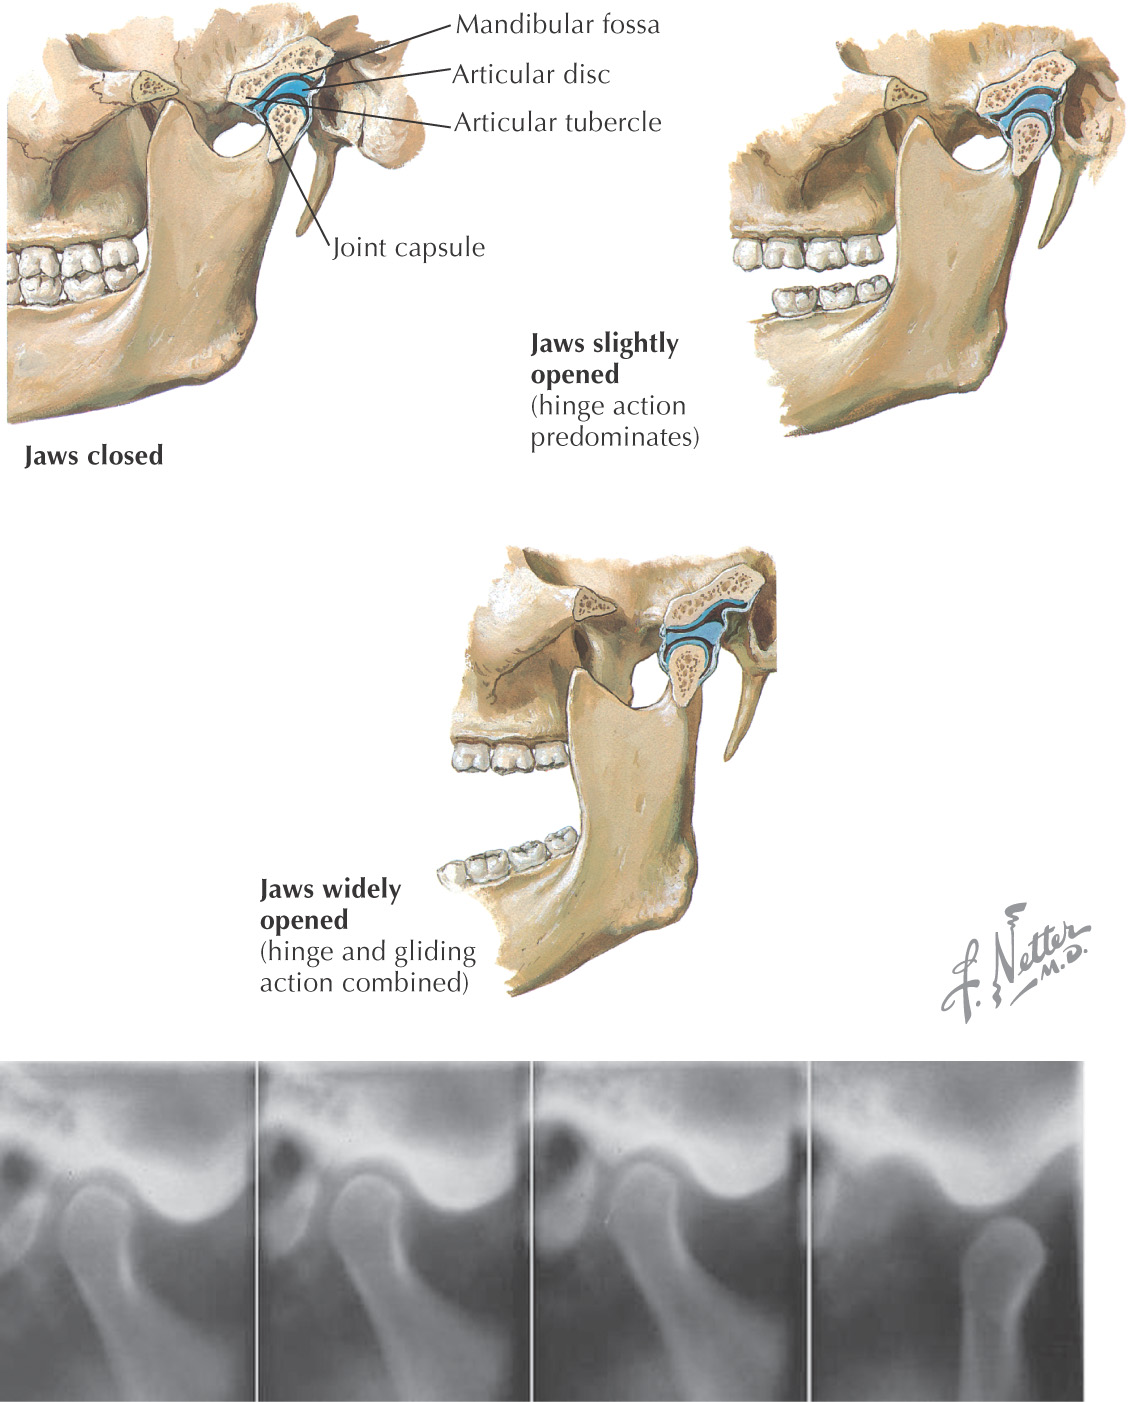

The temporomandibular joint (TMJ) is the articulation between the squamous portion of the temporal bone and the condyle of the mandible

The TMJ comprises 2 types of synovial joints—hinge and sliding—and consists of the following:

Opening the mandible involves a complex series of movements

Initial movement is rotational, which occurs in the lower TMJ compartment:

• As the mandible is depressed, the medial and collateral ligaments tightly attach the condyle to the articular disc, thereby allowing only for rotational movement

• Once the TMJ becomes taut, no further rotation of the condyle can occur

• Normally, rotational movement continues until the upper and the lower teeth are about 20 mm away from each other

For additional movement of the mandible, translational movement must occur:

• A translational movement occurs in the upper TMJ compartment and provides for most of the mandible’s ability to open

• In this movement, the articular disc and the condyle complex slide inferiorly on the articular eminences, allowing for maximum depression of the mandible